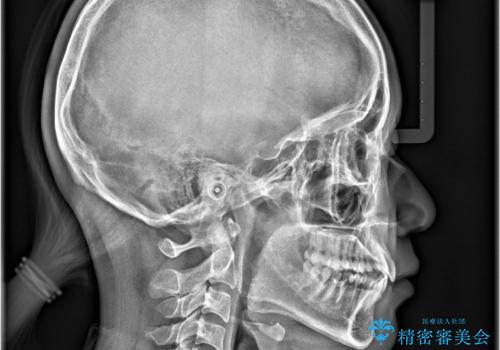

非抜歯矯正で八重歯を改善|短期間8か月で美しい歯並びに|インビザラインライト上顎のみで矯正

- 「八重歯を治したい」との主訴でご来院された患者様です。。

非抜歯で上顎のみインビザラインライトを使用して矯正を行いました。

短期間(約8か月)の治療で歯並びが整い、患者様も大変喜ばれました。